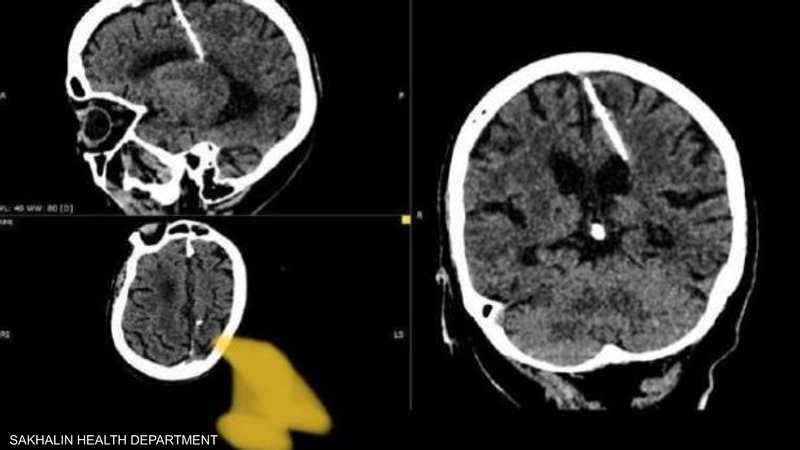

عثر أطباء خلال فحص بالتصوير المقطعي على إبرة بطول ثلاثة سنتيمترات موجودة منذ ثمانين عاماً داخل دماغ امرأة مسنّة في أقصى الشرق الروسي.

وقالت إدارة الصحة المحلية “لقد اخترقت الإبرة الفص الجداري الأيسر، لكن لم يكن لها التأثير المقصود، إذ نجت الفتاة”.